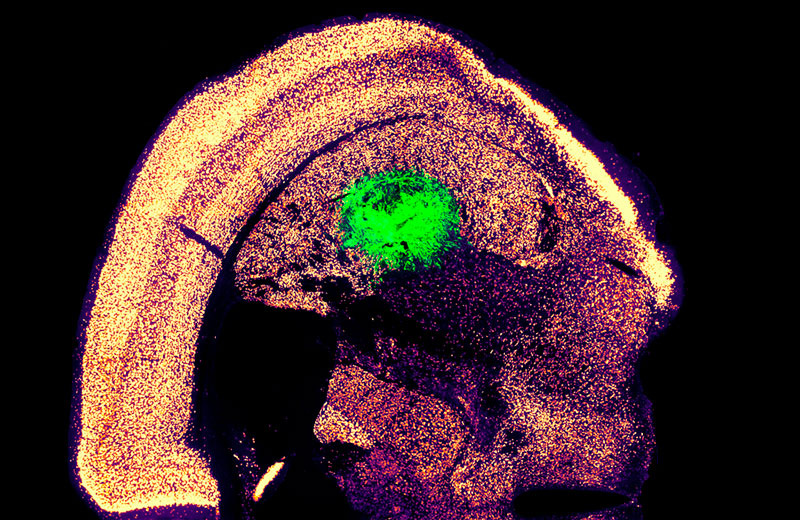

Folosind doar trei factori de transcripție, precum și alte două gene care promovează proliferarea celulară, au reușit să transforme celulele pielii șoarecilor în neuroni motori. Acest lucru a dus la formarea a peste zece neuroni dintr-o singură celulă a pielii, o creștere de 1.100% față de alte metode.

După testarea diferitelor sisteme de transmitere virală, echipa a descoperit că retrovirusurile sunt cele mai eficiente. În plus, reducerea densității celulare în cultură a îmbunătățit și mai mult rata de conversie, permițând producerea rapidă a unui număr mare de neuroni în doar două săptămâni.